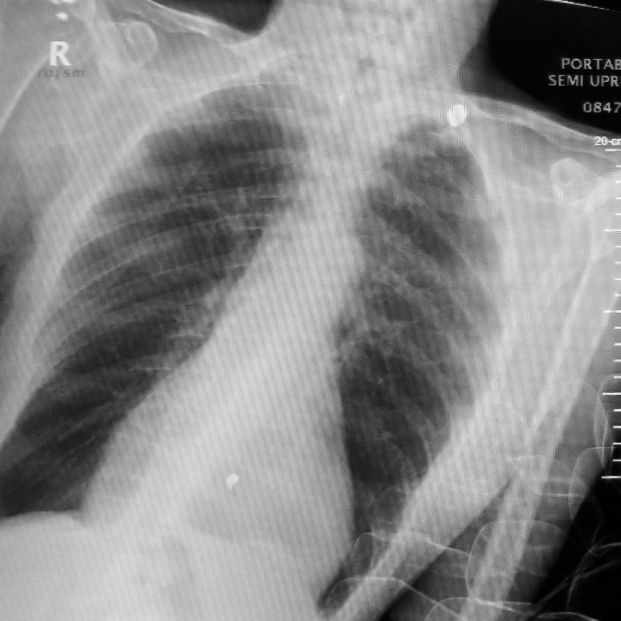

El futuro ha llegado. Gracias a una Inteligencia Artificial, investigadores norteamericanos son capaces de predecir el riesgo de muerte de una persona, haciendo uso de una única radiografía del tórax. Lo que hace unos años sería pura ciencia ficción, hoy se hace realidad gracias al desarrollo del aprendizaje en profundidad que utilizan este tipo de tecnologías novedosas.

Este modelo, presentado este martes 29 de noviembre en la reunión anual de la Sociedad Radiológica de América del Norte (RSNA), realiza una estimación a 10 años vista. Lo que calcula esta IA es la probabilidad de que el paciente sufra un ataque cardíaco o un derrame cerebral mortal debido a la acumulación de grasas y colesterol en las arterias, que se conoce de forma técnica como enfermedad cardiovascular aterosclerótica.

La principal mejora, que proporciona numerosas posibilidades, es que ahora solo se necesita una radiografía, que se adquiere millones de veces al día en todo el mundo, para realizar estas predicciones.